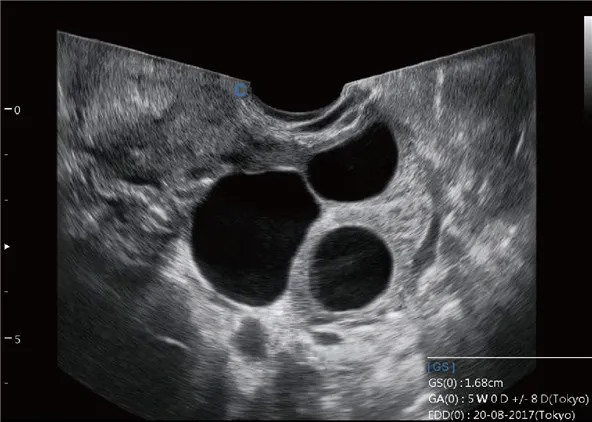

Sonda de TV de gran angular

● Ángulo extremadamente amplio de alrededor de 210°

● Proporcionar más información de diagnóstico

● Ahorre tiempo, mejore la eficiencia